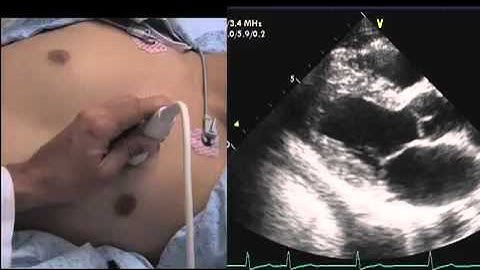

Intro to Echo Parasternal Views.mov